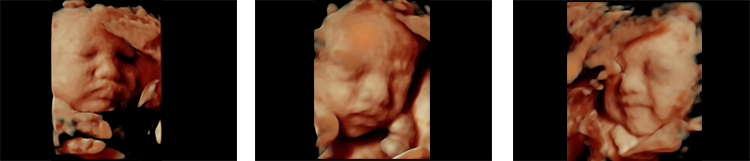

4D超音波は超音波映像を立体的に表現した3Dに、時間軸をプラスし、さらにリアルな動きを観察できるようにしたものです。

妊娠8週前後からお腹の赤ちゃんの様子を観察できるので、診察の場で活用しています。皆様により分かりやすい映像をご提供できるだけでなく、早期の胎児異常や、臍帯(さいたい)の位置などを知る手かがりにもなります。

4D超音波画像をクリックして頂くと、動画がご覧頂けます。

当院では、HD Live機能を搭載した超音波を導入しています。HD Liveでは、胎児の立体像を内視鏡画像のようにリアルに表現することができ、特に妊娠初期の診断に効果を発揮します。